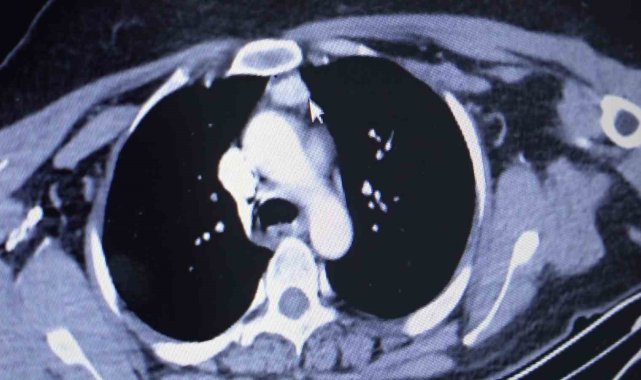

Amasya'da ayak tabanındaki yanma ve kaşıntıların giderek artması şikayetiyle hastaneye başvuran kadına, 100 binde 1 kişide görülen bir hastalığın teşhisi konuldu. Vücuda kalsiyum salgılayıp düzeyini kontrol eden 4 paratiroid bezinden biri, normalde olması gereken boyun yerine hastanın kalbinin üstünde bulundu. 3,4 kat büyümesiyle hastanın sağlığını tehdit eden kitle, başarılı bir ameliyatla alındı.Amasya'nın Göynücek ilçesine bağlı Karaşar köyünde yaşayan evli ve 3 çocuk annesi Emine Şahin'in Amasya Üniversitesi Sabuncuoğlu Şerefeddin Eğitim ve Araştırma Hastanesi'nde yapılan kontrollerinde normalde boyun kısmında olan paratiroid bezlerinizden biri göğüs kafesi içinde kalbe yakın bir noktada tespit edildi. Amasya Üniversitesi Tıp Fakültesi Dekanı Prof. Dr. Cafer Polat, Dr. Öğretim Üyesi Suat Evirgen ve göğüs cerrahisi ekibinin katılımıyla gerçekleştirilen ameliyatla kitle vücuttan çıkarıldı. 50 yaşındaki hasta şikayetlerinden kurtularak sağlığına kavuştu.Dr. Evirgen, "100 binde 1 kişide ender rastlanan ve bölgemizde ilk defa yapılan bir ameliyatı gerçekleştirdik. Çünkü Emine hanımın paratiroid adenomu normalde bulunması gereken boyun bölgesinde değil de göğüs boşluğu içindeydi. Bu bezler vücuda hormon salgıladığı için kemik erimesine, kanda kalsiyum artışına sebep oluyor. Bu tür hastalardaki şikayetlerin sebebi de zaten bu bezlerin büyümesidir" diye konuştu.Evirgen, eski sağlığına kavuşan hastanın ses tellerinde de herhangi bir problemin bulunmadığını sözlerine ekledi.

Amasya'da ayak tabanındaki yanma ve kaşıntıların giderek artması şikayetiyle hastaneye başvuran kadına, 100 binde 1 kişide görülen bir hastalığın teşhisi konuldu. Vücuda kalsiyum salgılayıp düzeyini kontrol eden 4 paratiroid bezinden biri, normalde olması gereken boyun yerine hastanın kalbinin üstünde bulundu. 3,4 kat büyümesiyle hastanın sağlığını tehdit eden kitle, başarılı bir ameliyatla alındı.